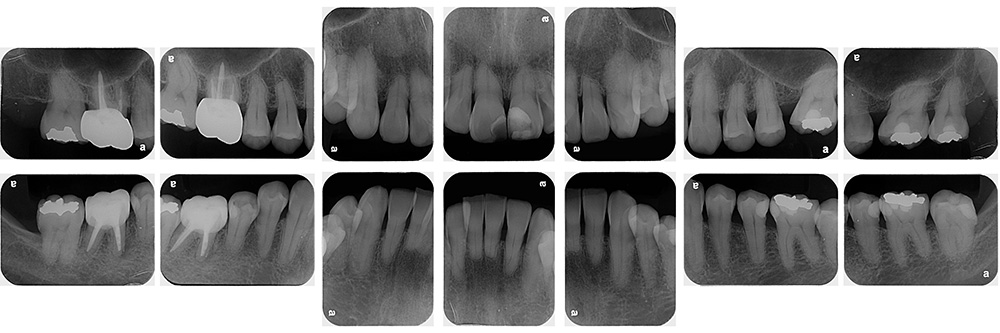

術前

術後

世代・性別

60代男性

主訴

歯ブラシで出血するので見てほしい

治療内容

ブラッシング指導、歯周基本治療、虫歯治療、根管治療、補綴治療

治療期間

6ヶ月

治療費

保険適応内

治療のリスク

治療後にしみる・痛みが出ることがある